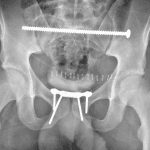

- Widening of the pubic symphysis to 1.3 cm

- Mild diastasis of the left sacroiliac joint

- Offset of multiple right sacral arches

- Excreted contrast material in the urinary bladder, which is slightly displaced to the right

- Unstable pelvic ring injury (APC II)

Unstable pelvic ring injury with diastasis of the pubic symphysis and left sacroiliac joint (APC II).

Offset of multiple right sacral arches concerning for right sacral fracture.

Slight rightward displacement of the urinary bladder may relate to mass effect from a left pelvic hematoma.